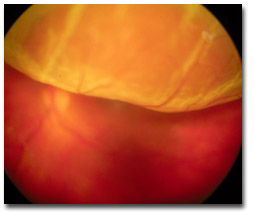

iii. Retinal detachment: classification, predisposition, recognition and urgency of treatment; recognition of proliferative vitreoretinopathy.